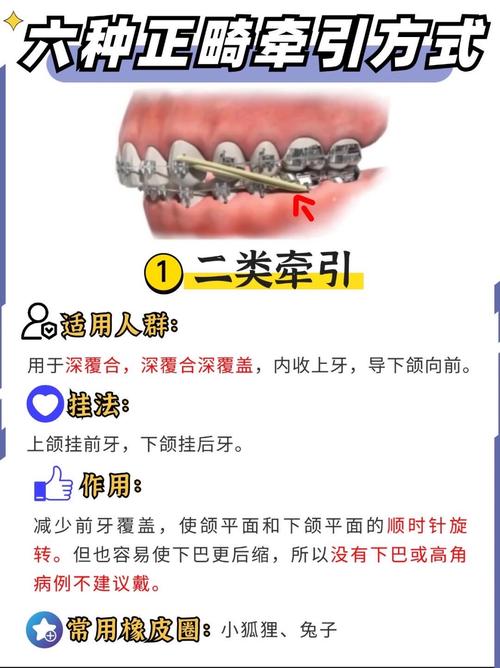

根据设计原理、固位方式及适应症,正畸下颌牵引装置可分为功能性矫治器、固定矫治器辅助牵引装置及活动式牵引装置三大类,具体特点如下表所示:

| 类型 | 代表装置 | 设计原理 | 适用情况 | 优缺点 |

|---|---|---|---|---|

| 功能性矫治器 | Activator、Twin-block | 利用肌肉力量传递牵引力,通过上下颌咬合板引导下颌位置,无需严格固位 | 替牙期或恒牙早期骨性III类错颌、下颌后缩;功能性下颌后缩 | 优点:无需粘接,患者适应性较好;缺点:依赖患者配合,效果不稳定 |

| 固定矫治器辅助牵引 | 颌间牵引、颏兜 | 通过固定矫治器(如方丝弓、直丝弓)的附件或口外弓施加牵引力,或联合颏兜牵引骨性III类、下颌发育过度 | 恒牙期患者;需精确控制牙齿移动与颌骨位置;骨性III类需术前术后辅助 | 优点:牵引力控制精确,效果稳定;缺点:需依赖患者配合佩戴口外装置,舒适度较低 |

| 活动式牵引装置 | FR-III、Herbst装置 | 活动基托固位,通过弹簧、弹力筋等提供牵引力,可单独使用或与固定矫治器联合 | 混合牙列期早期干预;需兼顾牙齿移动与颌骨调整;青少年患者 | 优点:兼具活动与固定优势,可调整牵引力;缺点:装置结构复杂,制作精度要求高 |